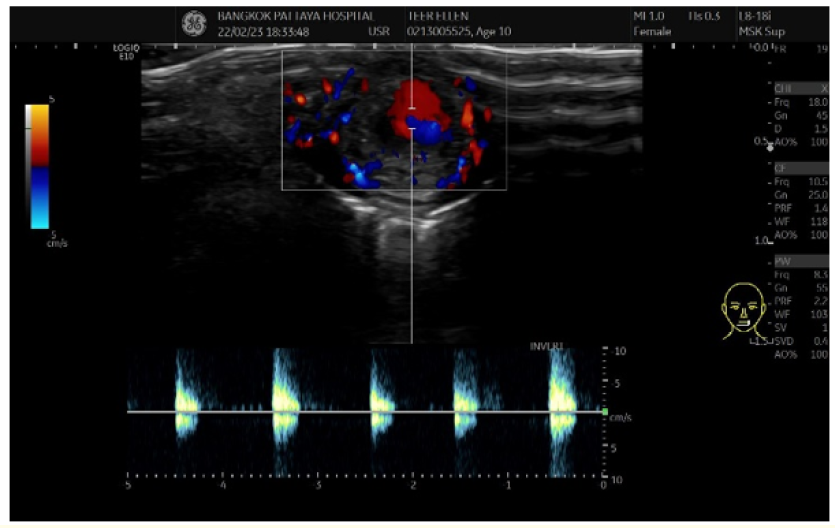

Post Traumatic Inferior Labial Artery Pseudoaneurysm After Lip Laceration: Case Report

Napasorn Phutong, Weeravit Ruangsirinusorn and David Limkul. 12(4): 65-67.